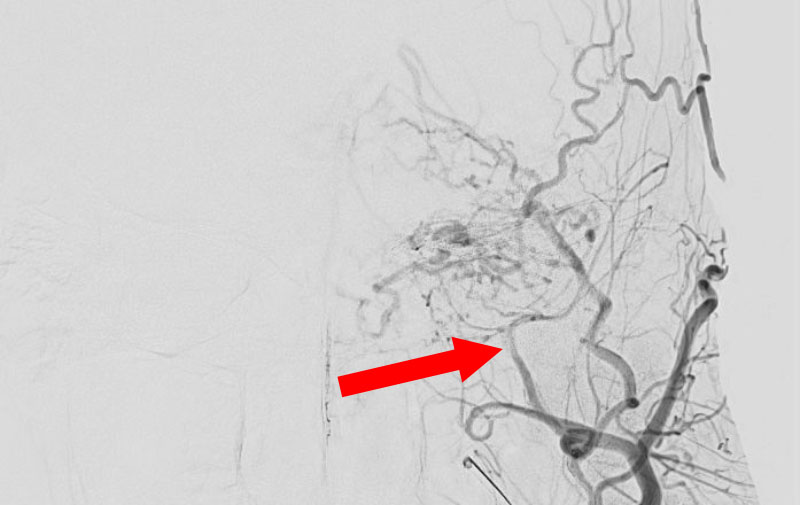

No.1591 手術前

硬膜動静脈瘻

50代

救急外来